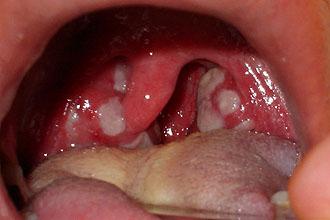

На начальном этапе заболевания воспаление в первую очередь затрагивает устья лакун, после чего налет или гнойный экссудат распространяется по всей поверхности гиперемированных миндалин. Налет проявляется в виде островков или пленки желтовато-белого цвета, имеющей рыхлую текстуру. Удалить этот налет не составляет особого труда. Эпителиальная ткань под налетом воспалена, но не имеет признаков некроза или повреждения сосудов.

Чтобы лучше понять, что такое лакунарная ангина и как она выглядит, полезно ознакомиться с фотографиями, которые наглядно демонстрируют изменения в лимфоидной ткани. Самостоятельно установить диагноз ангины сложно, поэтому для его подтверждения потребуется консультация врача и визуальное обследование глотки.